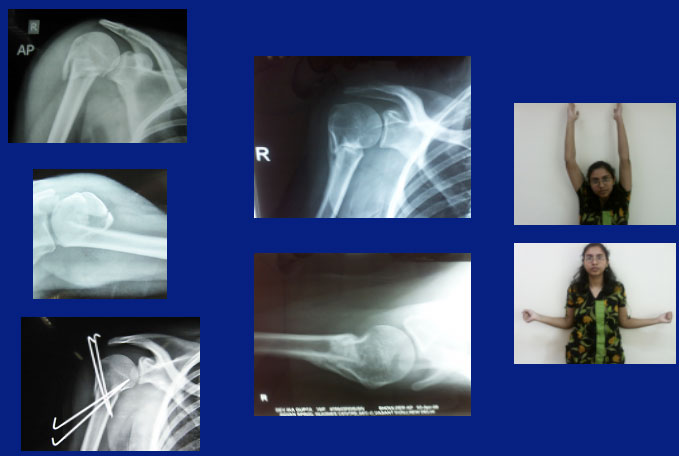

We have an expertise in re-doing old operated fractures, and those which have not been treated properly, in the first place. The following are some of the examples: